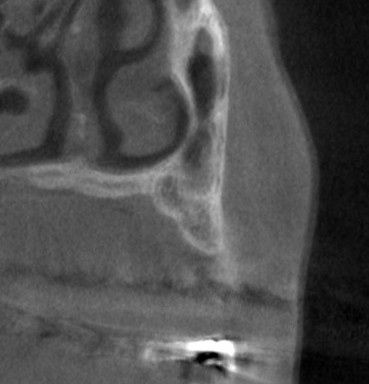

左臼歯に、3歯は必要と思われましたが、CTを見ると、1本目は骨の幅が狭く、2本目、3本目は骨の高さが足りません。

薄いところでは1mm程しかありませんでした(下の写真、2段目)。